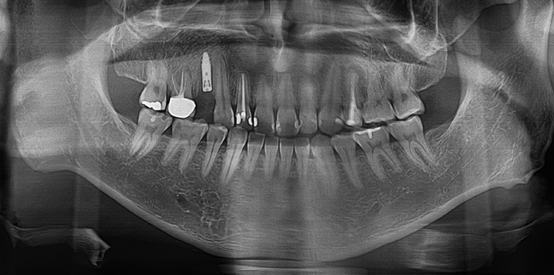

↑這是牙根斷裂的X光

當初因為不重視醫師的建議,導致牙齒需要拔除;所以這次很認真的聽取郭醫師的意見,有問題時郭醫師也會耐心回答。牙齒拔除後,可以選擇做假牙或是植牙,在眾多考量下,最後我選擇植牙。在等待看診時,老婆有跟我說郭醫師是專業的植牙醫師,具有10幾年的植牙經驗,加上岳父、岳母平時都是給郭德樑醫師看牙的,讓我對郭醫師的技術更加放心!

↑拔牙兩個月後待傷口平整,進行第二次的植牙評估,測量齒槽骨的寬度與深度是否適合植牙。郭醫師說這個階段很重要,若是齒槽骨的條件不理想,容易影響植牙成效;安全的植牙範圍在於齒槽骨需要有足夠的寬度和深度,骨頭密度也要達到一定的標準!